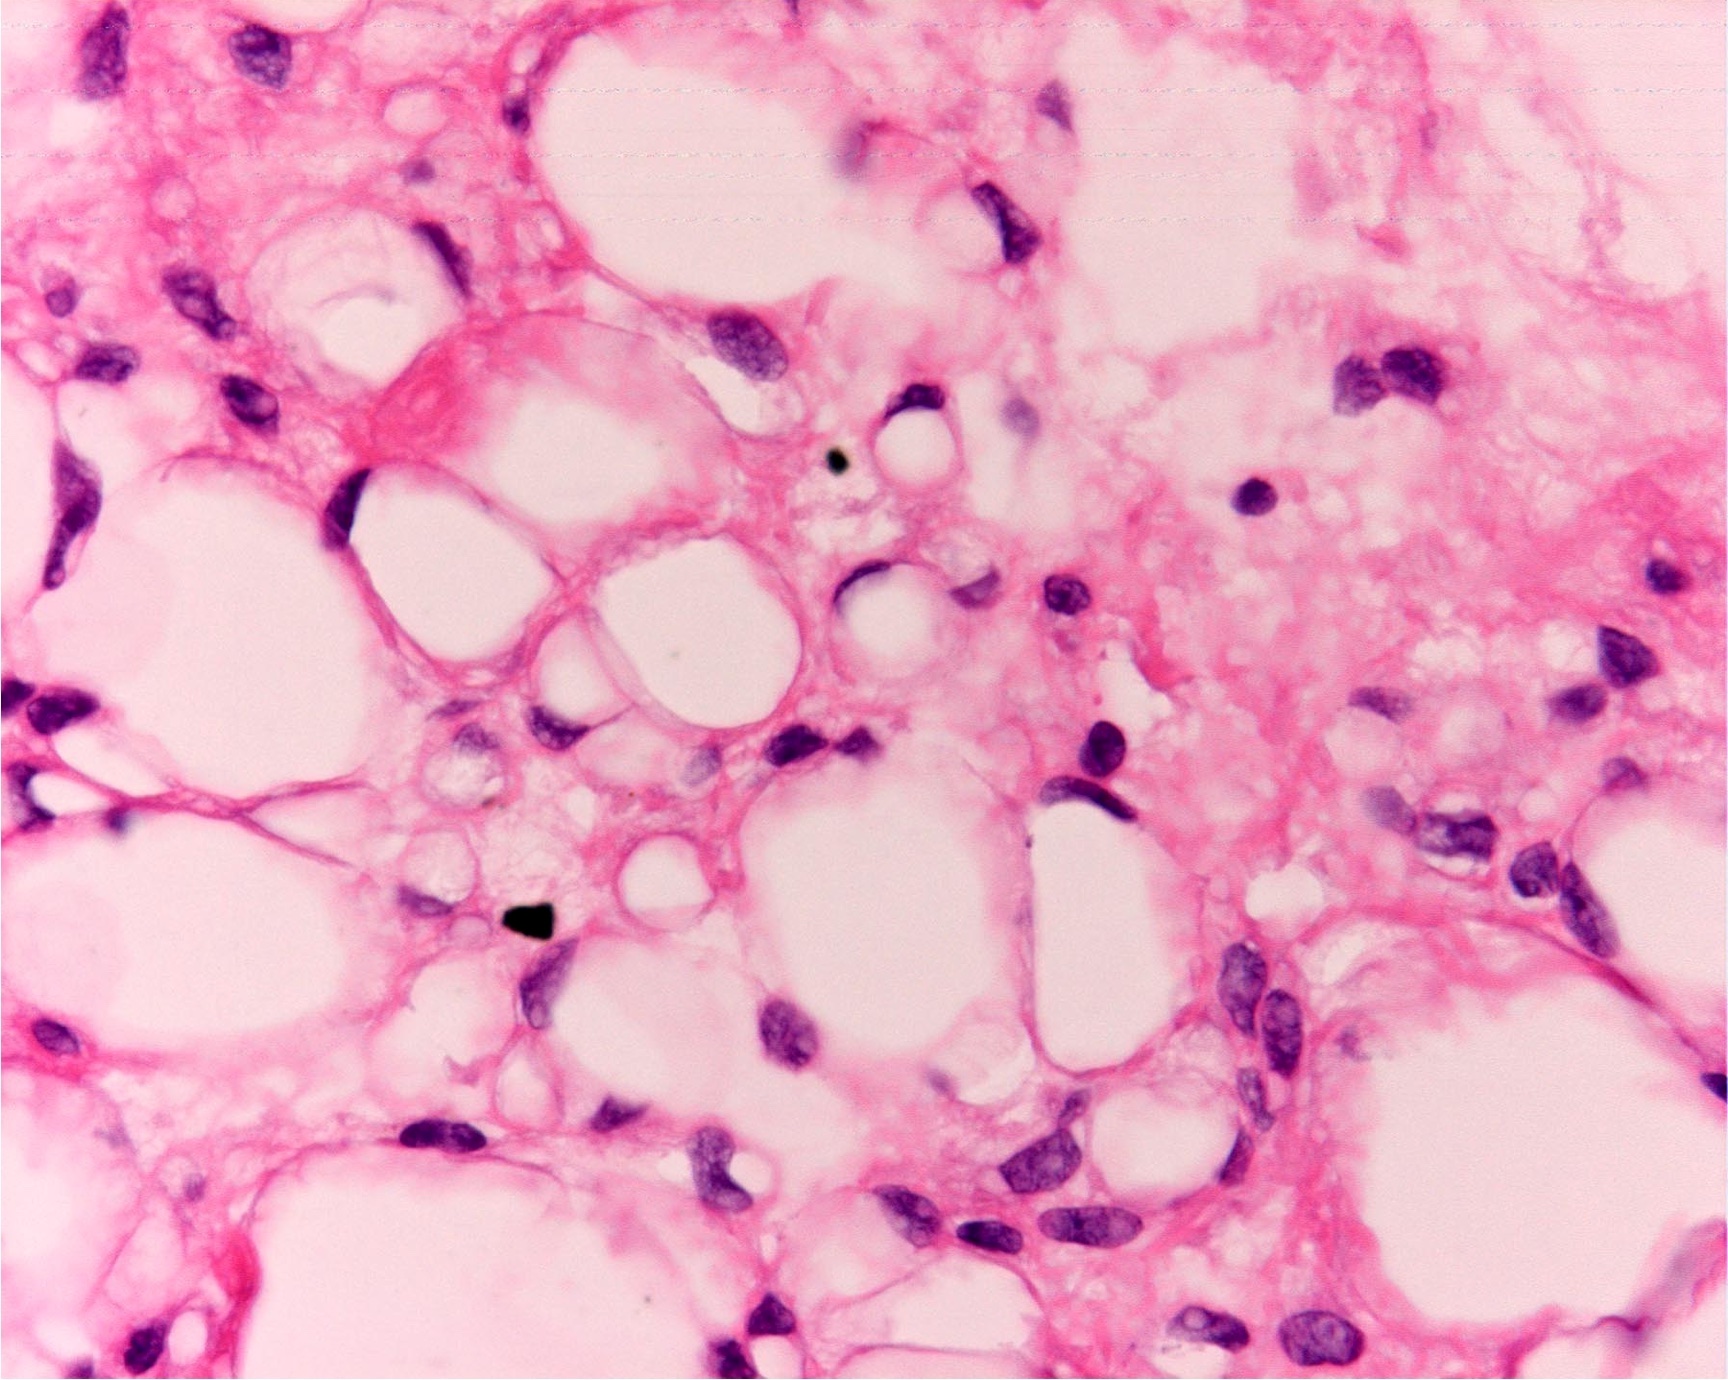

- Low grade

- Paucicellular with monomorphic, stellate or fusiform shaped cells without atypia; striking in their blandness, so much so that any significant pleomorphism should cause one to pause

- Prominent plexiform vasculature (delicate thin walled arborizing and curving capillaries that form a network reminiscent of chicken wire fencing)

- These are striking because of the overall background paucicellularity and are still present in high grade tumors but are much less obvious

- Numerous signet ring lipoblasts, particularly at periphery of lobules

- This imparts a lipoblastoma-like appearance (see Differential diagnosis)

- Mucoid matrix is rich in hyaluronic acid that may form large mucoid pools (so called pulmonary edema pattern)

- Will be positive for stromal mucin stains such as Alcian blue (see Microscopic (histologic) images)

The microscopic image above depicts the histologic appearance of a soft tissue mass resected from the thigh of a 37 year old man and is representative of the entire lesion. Which of the following is true regarding the diagnosis?

D. Majority of cases harbor t(12;16) FUS::DDIT3 gene fusion. The microscopic image depicts a low grade myxoid liposarcoma characterized by a proliferation of bland stellate tumor cells embedded in a myxoid matrix with a prominent plexiform capillary network and scattered signet ring lipoblasts. There is no mitotic activity or pleomorphism. The majority of cases of myxoid liposarcoma harbor a t(12;16) FUS::DDIT3 gene fusion. Answers B and C are incorrect because the t(9;22) EWSR1::NR4A3 gene fusion is characteristic of extraskeletal myxoid chondrosarcoma and the t(7;16) FUS::CREB3L2 gene fusion is characteristic of low grade fibromyxoid sarcoma. Answer E is incorrect because classification of myxoid liposarcoma as high grade requires > 5% of the sampled lesion to consist of a hypercellular round cell component according to the WHO. Cases with borderline round cell component (< 5%) are regarded as having areas of transition, a designation of unclear diagnostic significance. Answer A is incorrect because immunohistochemistry for MDM2 is negative in myxoid liposarcomas.